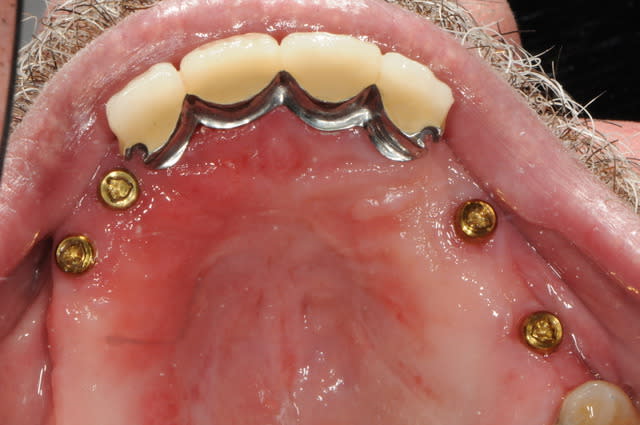

un ptit exemple...

( pardon , je l'avais déjà posté sur nonol mais je ne retrouvais plus le lien...)

pour la petite histoire, le patient voulait seulement une stabilisation de sa prothèse amovible.

les couronnes c'est moi qui lui ai imposé car il fallait rétablir un plan occlusale convenable.

comme les moyens financiers n'étaient pas au rdv une PACSI n'était pas possible.

sa mutuelle lui a très très bien pris en charge ses couronnes et une parti de ses implants. De plus il ne souhaitait vraiment pas extraire les dents antérieurs...

il est tout de même content, mais c'est parfois dure de trouver une solution qui puisse correspondre aux attentes du patient tout en prévoyant l'avenir. quand il le souhaitera, je mettrai deux implants de plus pour passer en prothèse fixe, et dans le pire des cas, pas d'implants supplémentaires, mais un complet stabilisé sur 4 implants.